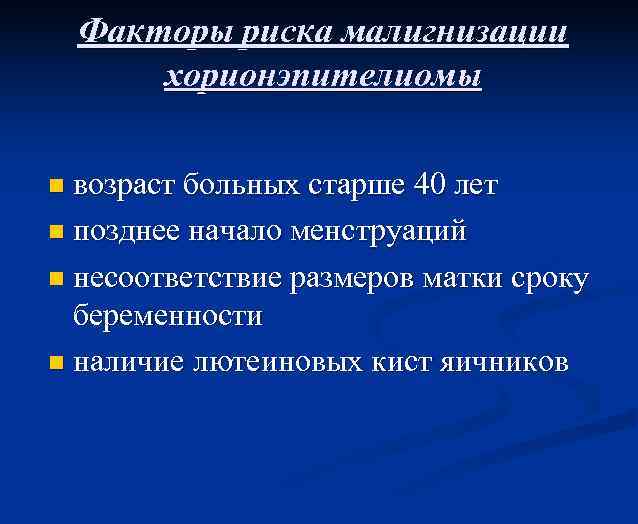

Факторы риска малигнизации хорионэпителиомы возраст больных старше 40 лет n позднее начало менструаций n несоответствие размеров матки сроку беременности n наличие лютеиновых кист яичников n